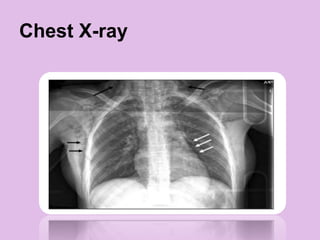

Chest X-ray